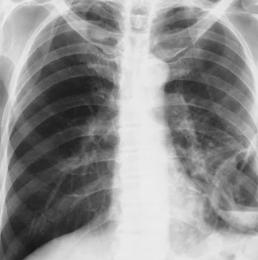

폐농양의 진단은 흉부 X-ray, CT, 객담 검사 등을 통해 이루어집니다. 흉부 X-ray나 CT를 통해 폐농양의 위치와 크기를 확인하고, 객담 검사를 통해 원인균을 파악하여 적절한 항생제를 선택할 수 있습니다.